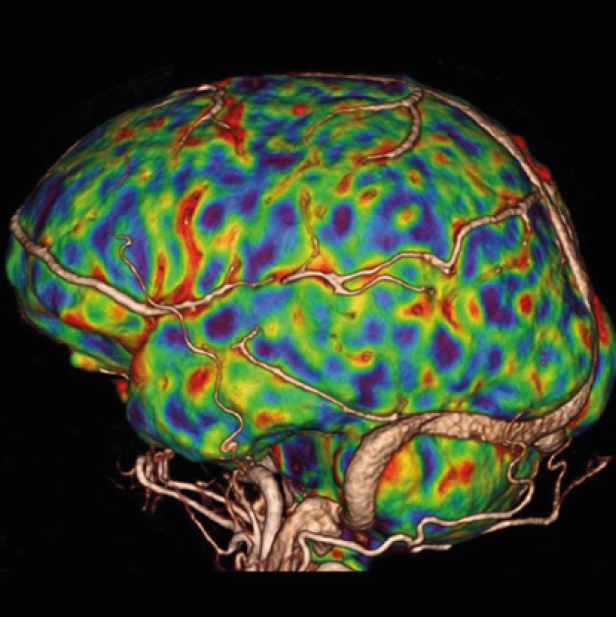

Наші КТ-сканери та програмне забезпечення для постобробки здатні створювати тривимірні зображення з високою роздільною здатністю, що, по суті, усуває попередні проблеми, пов’язані з візуалізацією перфузії. Обмеження часткового охоплення мозку КТ-перфузією було подолано завдяки введенню зонального детектора на Aquilion ONE та режиму "shuttle mode" в Aquilion Prime SP.

4D перфузія всього мозку